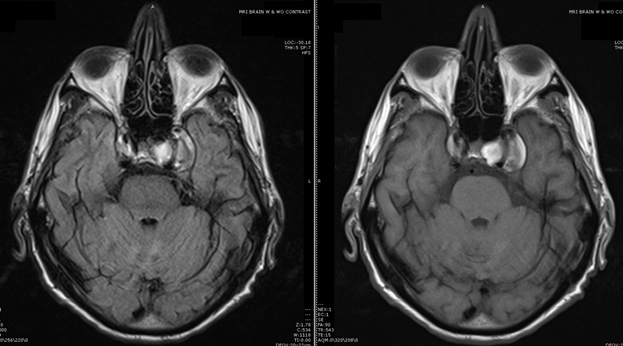

76 y/o M presented with 'double vision' and Left facial pain (V1, V2 and retro-orbital). CTA revealed b/l supraclinoid ICA fusiform aneurysms. Patient underwent coiling by IR with MRI below.

Exam shows OS ophthalmoplegia with minimal abduction, unable to open left eyelid (complete ptosis), dysthesia in Left V1 and V2, pupils are equal and some anhidrosis on the left forehead.

Consulted for procedural consideration secondary to intractable left facial pain unresponsive to neuromodulators and opioids...….If any, what is your intervention?